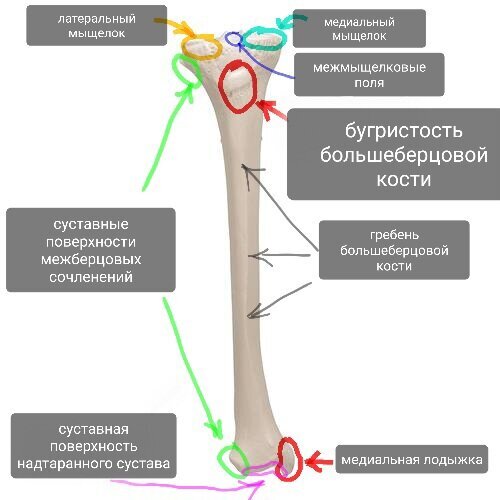

Проксимальный эпифиз сформирован медиальным и латеральным мыщелками, на которых расположены суставные поверхности, образующие большеберцовую часть коленного сустава. Между суставными поверхностями есть костные площадки - переднее и заднее межмыщелковые поля, к которым крепятся передняя и задняя крестообразные связки соответственно (внутренние связки коленного сустава).

В области медиального мыщелка находится точка крепления полуперепончатой мышцы.

Сбоку латерального мыщелка находится суставная поверхность проксимального (верхнего) межберцового сочленения (сустав с малоберцовой костью).

На задней поверхности зпифиза находится точка крепления подколенной мышцы.

По передней поверхности посередине, под мыщелками находится бугристость большеберцовой кости - костный ориентир, точка опоры (при опоре на колено), а также точка крепления одного из крупнейших сухожилий - собственной связки надколенника, также с медиальной стороны к ней подходит общее сухожилие полусухожильной, тонкой и портняжной мышц (так называемая гусиная лапка, о которой много знают те, у кого были травмы коленного сустава). С этой бугристостью связано немало проблем у юных спортсменов, об этом будет статья.

Важные элементы большеберцовой кости.

Передняя поверхность большеберцовой кости - гребень. Очень хорошо прощупывается под кожей. Кто хоть раз ударялся этим местом отлично помнит это место.

Нижний эпифиз сформировон медиальной лодыжкой - тоже костный ориентир. Косточка с внутренней стороны голеностопного сустава. Этим местом тоже больно ударяться, и тут может быть перелом или ушиб (при подворачивании стопы).

К медиальной лодыжке крепятся медиальная группа связок надтаранного сустава (дельтавидные связки).

С внутренней стороны располагается суставная поверхность дистального (нижнего) межберцового сочленения.

Нижняя плоскость большеберцовой кости - суставная поверхность надтаранного чустава. В этом месте осевая нагрузка с таранной кости почти полностью передаётся на большеберцовую.